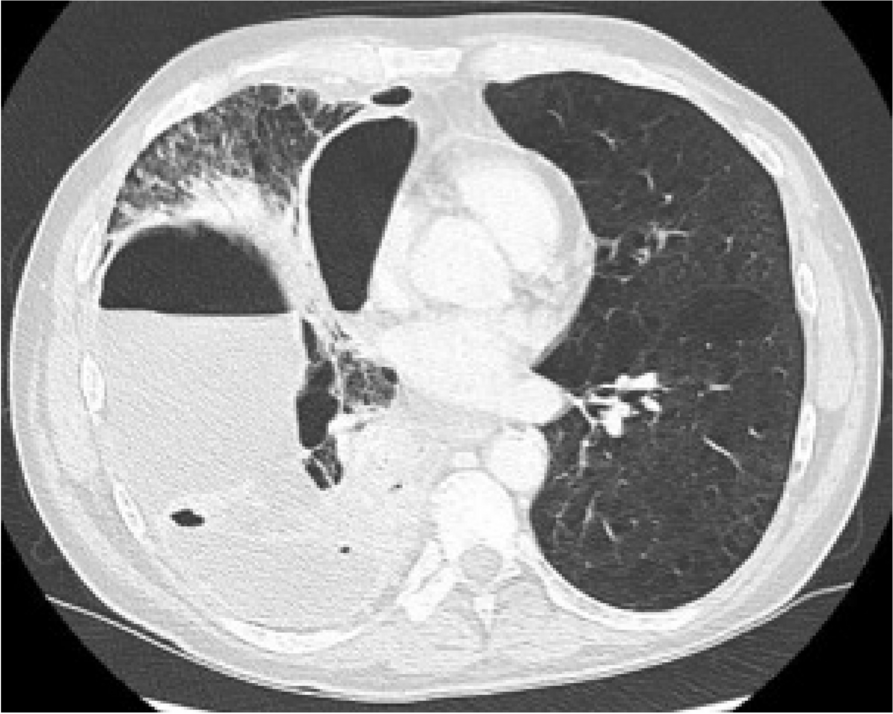

A few hours after the admission in ICU he reported a blunt abdominal pain, mainly on the right side, nausea and the exams showed increased amylase levels, urologists excluded any surgical involvement of pancreatic tissue and suspected a transient sphincter of Oddi dysfunction [3]. After one night in ICU he was transferred to the urology ward due to his clinical stability, even though Amylase peaked at 2340 U/l. Two days later abdominal pain increased to severe, with characteristics of peritonism and increased inflammatory markers. An abdomen-thorax CT scan revealed acute pancreatitis (AP) (Figure 1) and he was transferred to ICU. He started a standard treatment for acute pancreatitis and antibiotic therapy [4].

On postoperative day nine, due to general deterioration of clinical conditions and further anemization that required blood transfusion, he underwent an emergency laparotomy, in which propofol was not used as an anesthetic drug, that found a completely necrotic pancreas. The following day he faced a multi organ failure (MOF) which rapidly led to death. Consent to publish the case report was accorded by the family.

Acute pancreatitis (AP) Is a complex and severe disease with a high mortality rate [4]. Propofol, is a common anesthetic drug which is widely used in daily practice for sedations and general anesthesia [5], few cases of Propofol Induced AP have been published, in which the diagnosis has been made excluding more common causes [6].

In fact, Propofol is listed as a possible cause of AP, class Ib, based on the classification of Badalov et al. [7]. Following the scheme proposed by the systematic review by Haffar et al for Propofol induced AP [6] we could confirm that our hypothesis is plausible. He satisfied the American College of Gastroenterology criteria for AP [8,9] and it is classified as severe acute pancreatitis according to the Revised Atlanta Classification with peripancreatic necrotic fluid collection [10]. Marshall score [11] after admission was two and Naranjo et al [12] probability scale for drug adverse reaction was three, meaning that the adverse reaction is possible. Latence according to Badalov et al [7] has been short or intermediate. Exclusion of other plausible causes, timing of pancreatitis symptoms and previous cases in literature support our hypothesis of propofol induced pancreatitis.

Fig. 1 (abstract A21).

See text for description